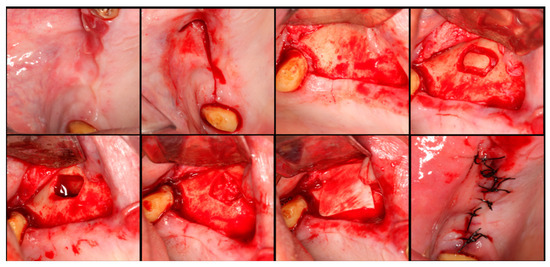

The surgical process, performed by the same surgeon, involved local anesthesia followed by incisions, flap detachment, osteotomy, and membrane elevation. Autologous bone from the mandibular branch (Figure 1) or the mental symphysis (Figure 2), or a porcine xenograft (Figure 3) were used as the graft materials for sinus augmentation. The protocol for this study involved using either two or three syringes of Oteobiol MP3, delivering a volume of approximately 2 to 3 cc per sinus. The contralateral sinus received a similar amount of autologous bone, either from the mental region (desmal with probably some bone of enchondral origin) or the mandibular ramus (desmal origin). Figure 3 and Figure 4 depict one example from each side of maxillary sinus augmentation treatment. Post surgery, the patients followed a prescribed protocol. After six months, a follow-up CT scan was conducted, and dental implants were placed. The final phase involved inserting healing abutments or prostheses, ensuring that no tooth–implant connections were established [20].

Figure 1. Surgical steps for harvesting autologous bone graft from the mandibular branch. In the first row, left to right: mandibular ramus, incision, flap detachment, and graft drilling. In the second row, left to right: graft removal, graft measurement, and sutures.